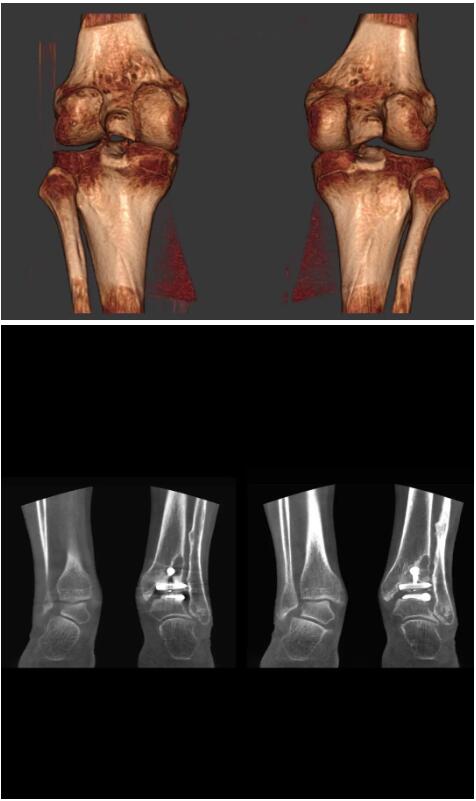

這款CT掃查系統(tǒng)自帶屏蔽裝置,它的體積非常小,僅需要極小的空間即可,并不像常規(guī)CT那樣需要一間單獨的檢查室。此外,這種CT掃查的速度非???,僅需30秒左右可以完成檢查,輻射劑量相對常規(guī)的CT要少許多,尤其適合醫(yī)院的骨科使用。

而患者站著做足部或者踝部做CT檢查還有個好處是,可以檢查患者在負重的情況下,骨關(guān)節(jié)的真實情況,而躺著做CT掃查時未必能看出來。負重CT掃查特別是對于受傷的運動員或者舞蹈員來說意義更大,能夠更準確地評估傷情,幫助他們盡早復(fù)原。

另外一款被稱為世界上最小的CT,它的重量僅300磅,不僅能夠掃查足部,還可以檢查膝蓋和上肢等。

與上面介紹的CT一樣,它同樣具有輻射低、占地空間小(23*36)的特點,隨開隨用(支持直接接入墻上的插座)。

這款CT使用非常方便,通過上下移動保持與患者的手臂或者雙腿齊平,掃描快速,僅需要30秒左右就可以完成掃查。

以上介紹的CT均來自國外同一家公司,這些CT均配置了可視化軟件,可以進行切片、3D重建以及大型CT附帶的所有典型的操作功能。

以下是這些“特立獨行”的CT所拍出來的圖像: